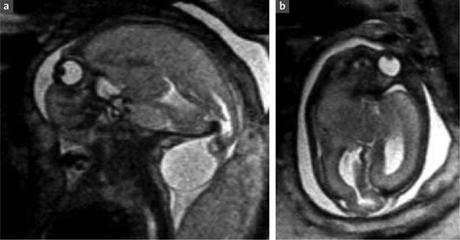

Défaut de morphogénèse médullaire. In Imagerie de la Femme Volume 18, Issue 3, September 2008, Pages 157 - 164